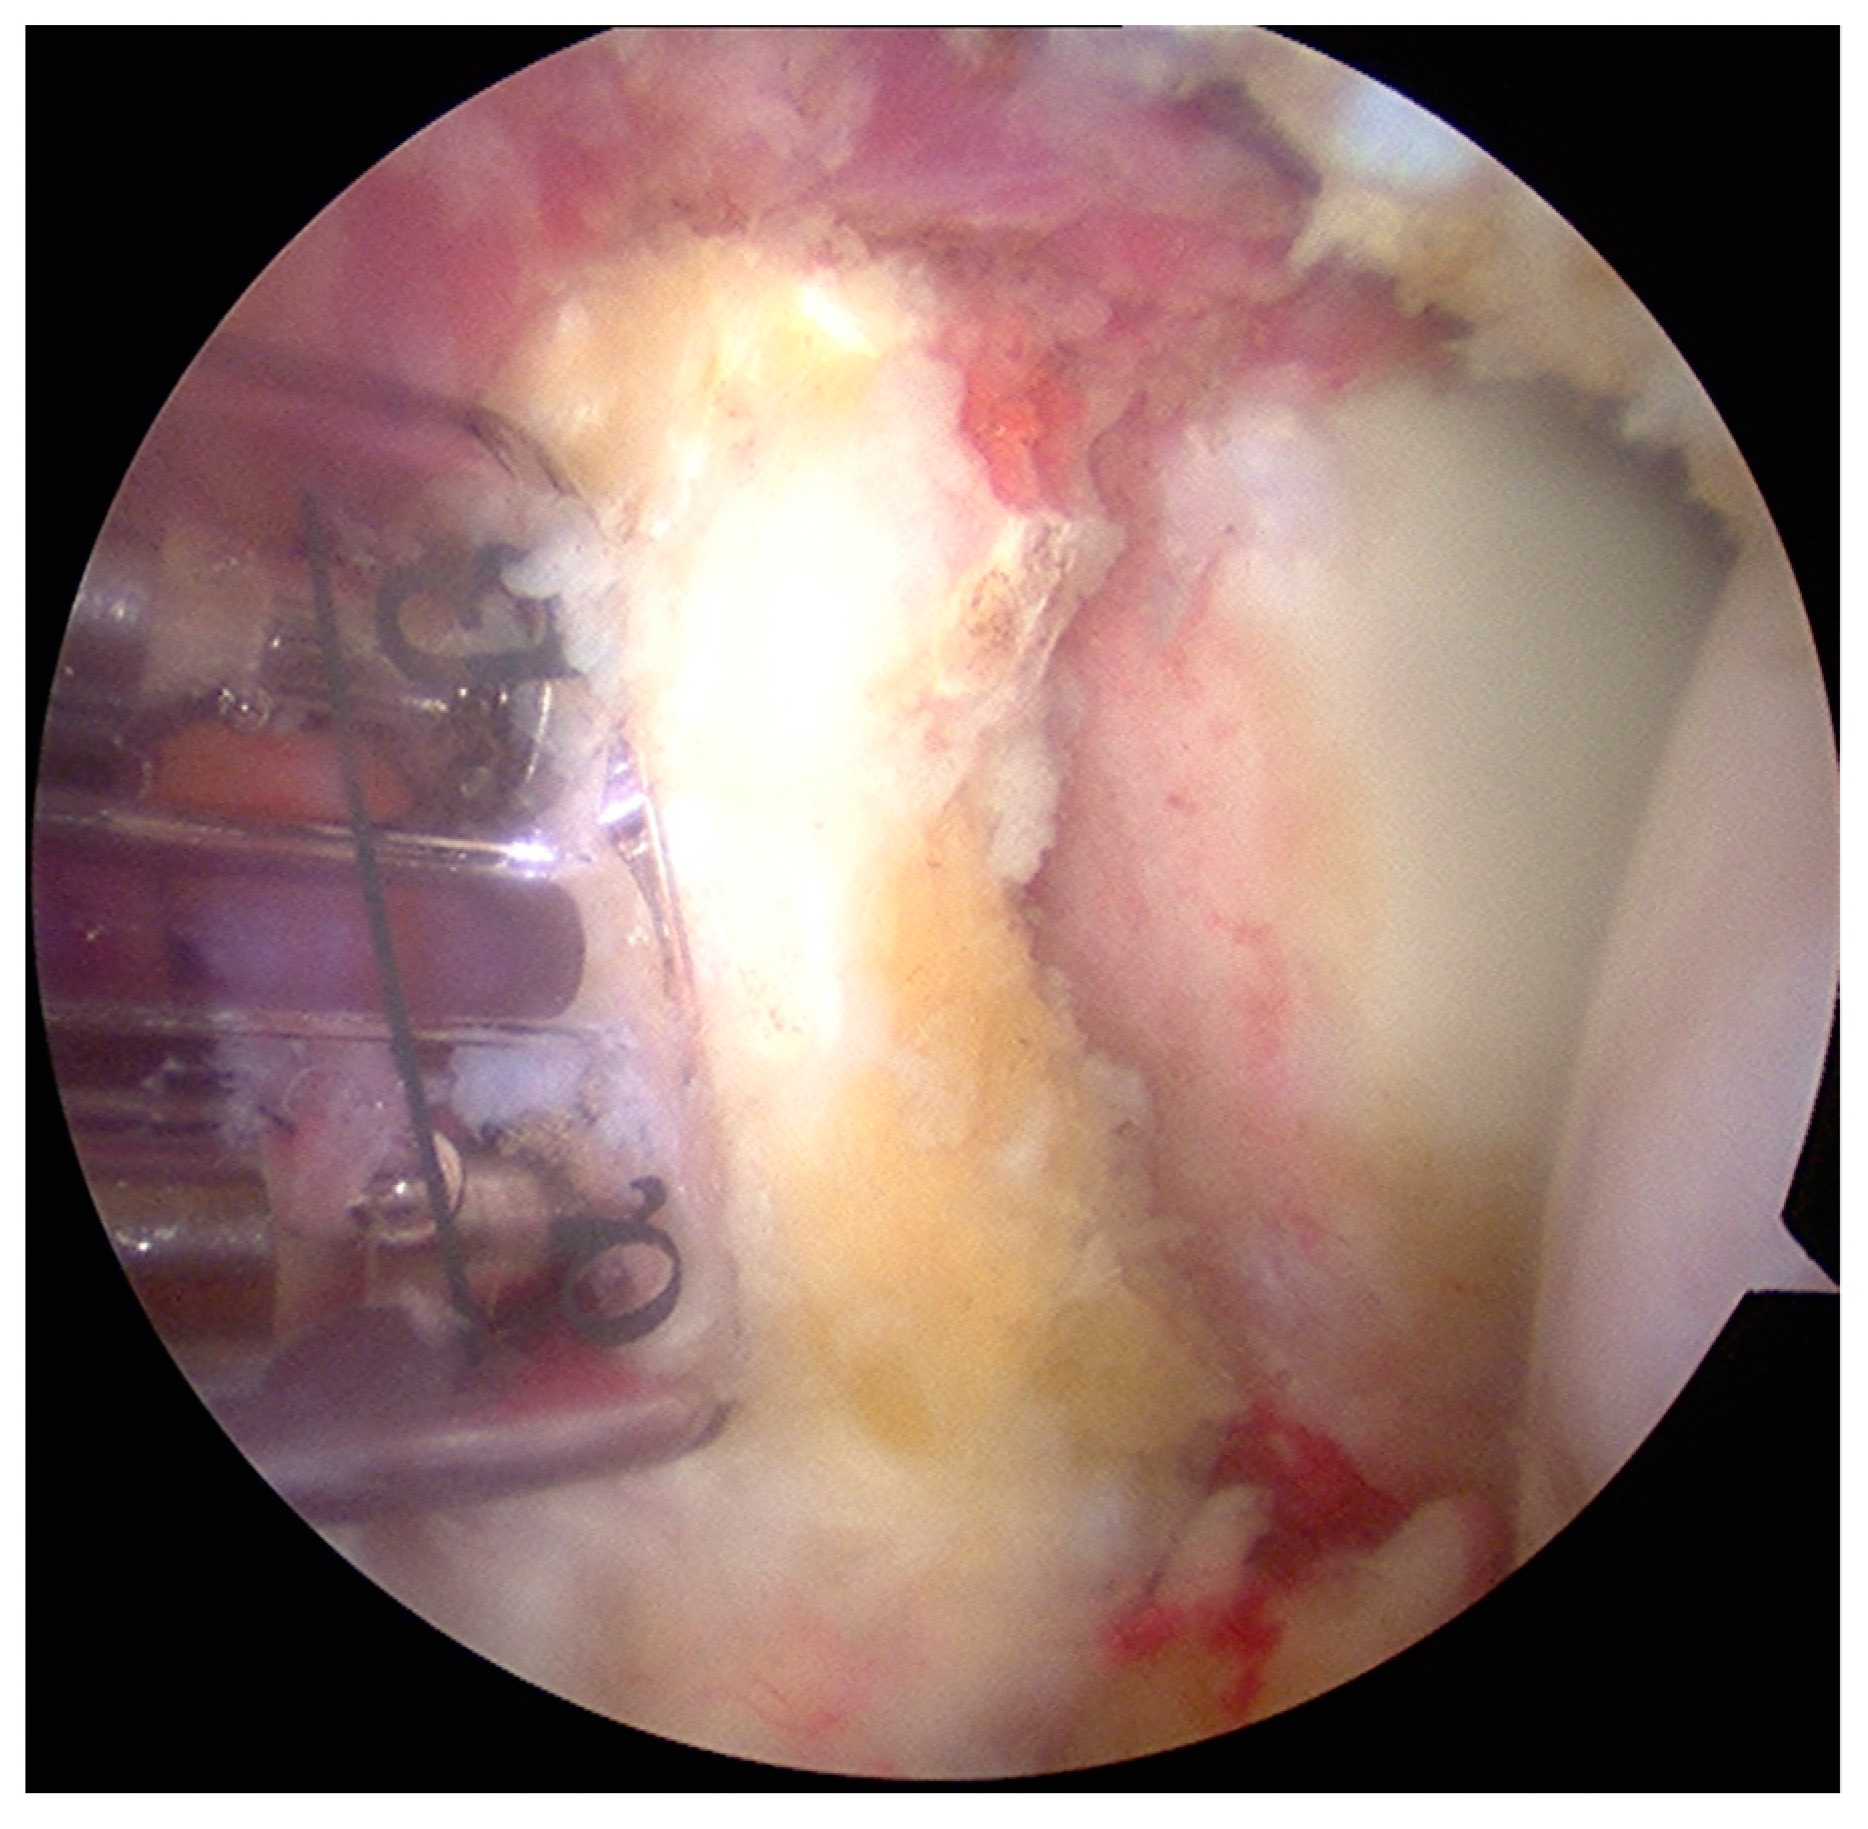

- The graft was positioned on the anterior glenoid neck with the switching stick through the posterior portal (Figure 3).